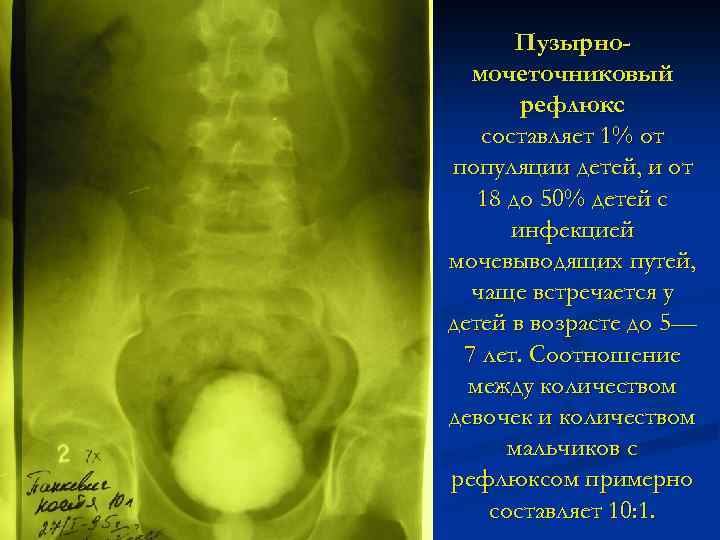

Рефлюксирующий мегауретер: Визуализация и медицинские изображения